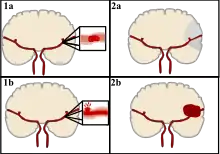

There are two main categories of strokes. Ischemic (top), typically caused by a blood clot in an artery (1a) resulting in brain death to the affected area (2a). Hemorrhagic (bottom), caused by blood leaking into or around the brain from a ruptured blood vessel (1b) allowing blood to pool in the affected area (2b) thus increasing the pressure on the brain.

Strokes can be classified into two major categories: ischemic and hemorrhagic.[18] Ischemic strokes are caused by interruption of the blood supply to the brain, while hemorrhagic strokes result from the rupture of a blood vessel or an abnormal vascular structure. About 87% of strokes are ischemic, the rest being hemorrhagic. Bleeding can develop inside areas of ischemia, a condition known as "hemorrhagic transformation." It is unknown how many hemorrhagic strokes actually start as ischemic strokes.[2]